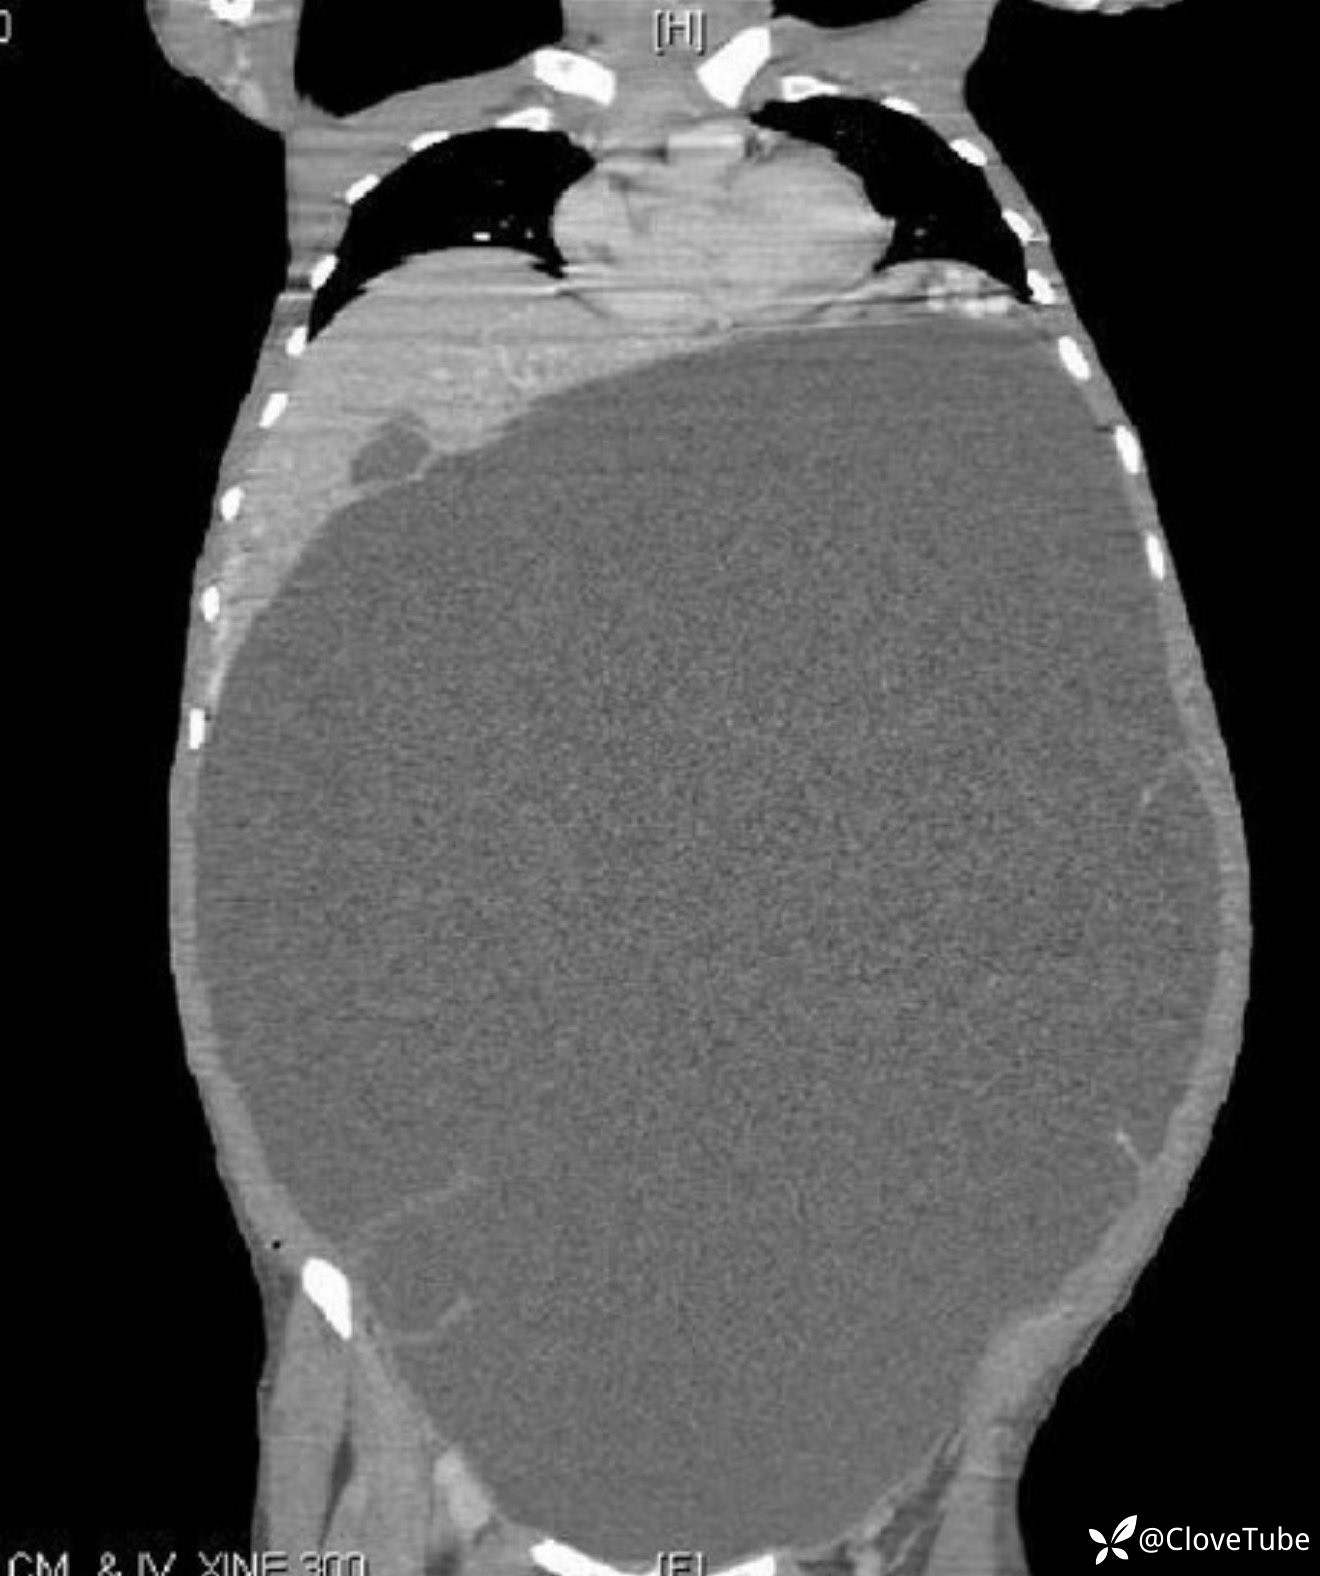

女 40y 腹胀进行性加重